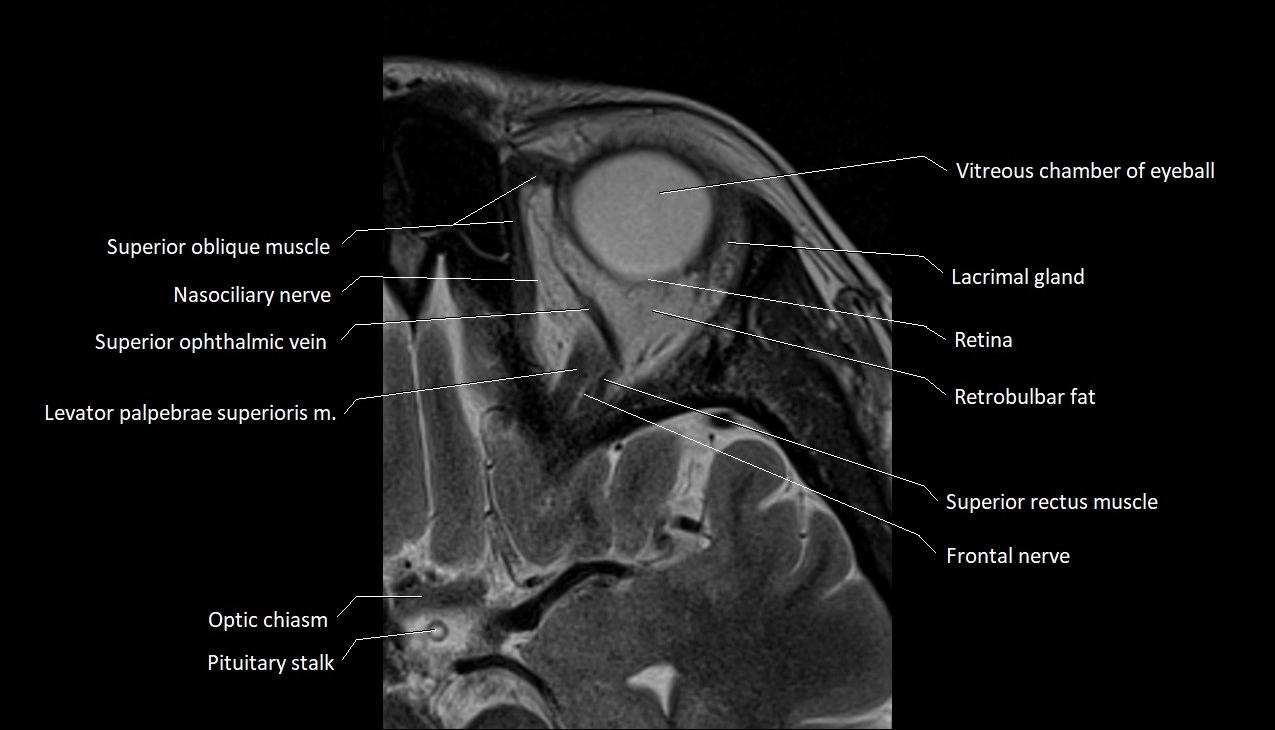

- Superior oblique muscle

- Superior ophthalmic vein

- Frontal nerve

- Levator palpebrae superioris muscle

- Lacrimal gland

- Retina

- Retrobulbar fat

- Superior rectus muscle

- Optic chiasm

- Vitreous chamber of eyeball